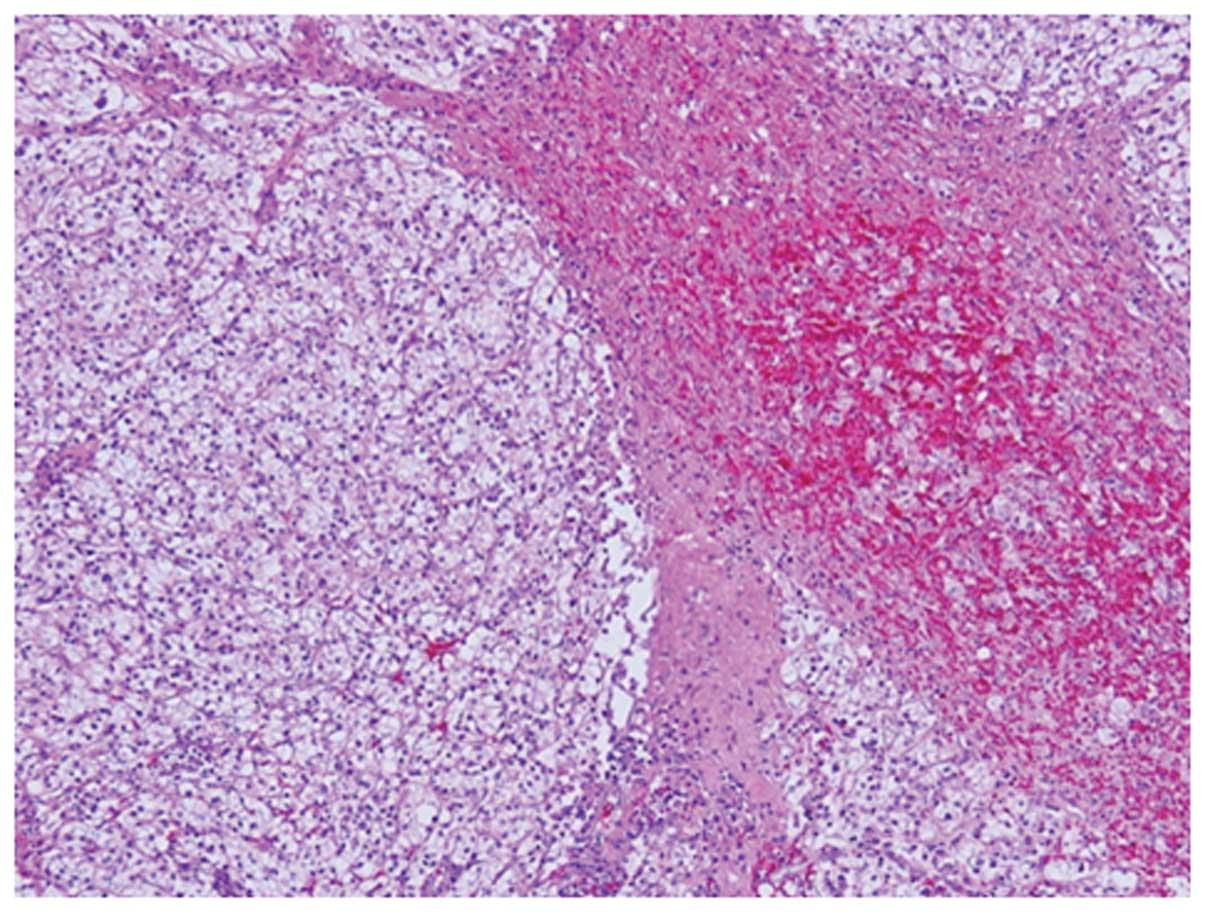

In general, only ≤5% of patients with renal cell carcinoma (RCC) develop paraneoplastic erythropoietin (EPO) overproduction‑induced polycythemia. However, a number of reports on EPO‑producing RCC are available. The present study aimed to report the first case of a patient demonstrating a therapeutic effect on EPO‑producing advanced RCC, subsequent to targeted pre‑surgical sunitinib therapy, with a review of the literature. The patient involved was a 62-year-old male who presented with a malformation of the left scrotum. Examination revealed a tumor of 73 mm in diameter along with lymph node metastasis. The histological examination indicated a clear cell RCC containing viable cells as well as hemorrhage and necrosis. EPO in cancer cells was confirmed by immunohistochemistry. Subsequently, a case of EPO-producing RCC with polycythemia was diagnosed. The EPO-producing RCC was successfully treated following targeted presurgical therapy with sunitinib.